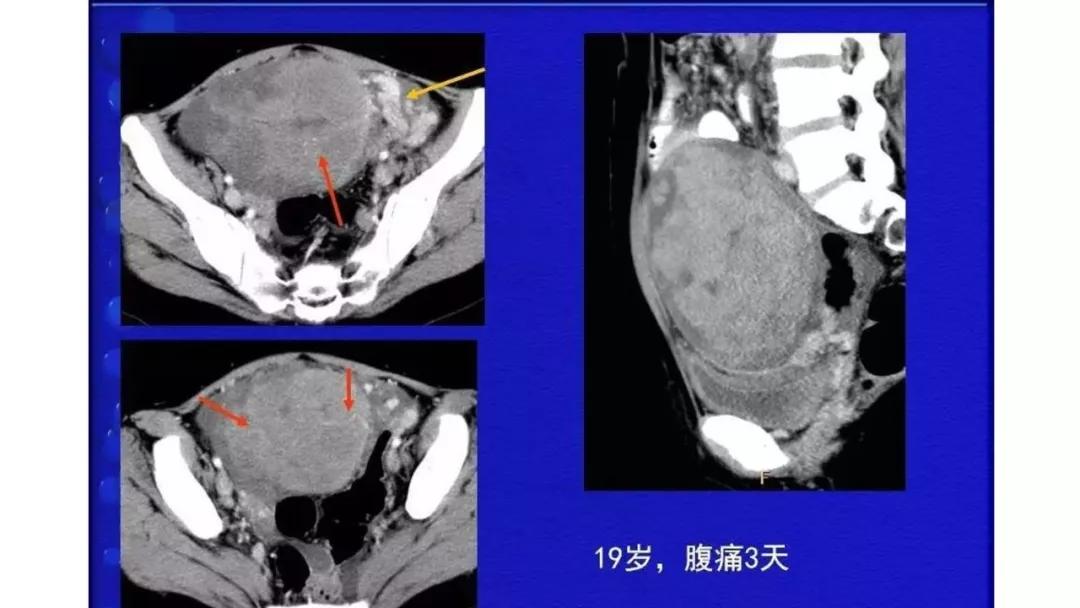

恶性者常呈实性或混杂性肿块,多数边界清楚,可伴有不规则沙粒状钙化。无性细胞瘤常为实性肿块,轻度强化,内胚窦瘤实性成分明显强化,不成熟畸胎瘤呈混杂密度。结合年龄及临床生化检查,有助于诊断。